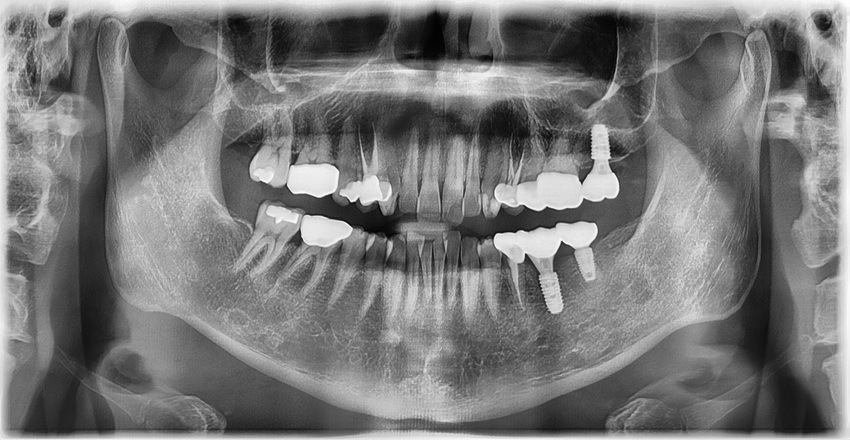

The greatest advantage of immediate implant placement after extraction is the reduction in overall treatment time. It shortens the waiting period after extraction by several months, minimizing the time the patient has to live without a tooth. In addition, it can help prevent rapid resorption of the alveolar bone to some extent, making immediate implant placement a good option when conditions are suitable. Furthermore, because the number of surgical procedures is reduced, the burden on the patient is relatively lower. After waiting approximately three months to allow the implant to fully integrate with the bone, we confirmed stable osseointegration and completed the final crown.

Compared to the previously placed implant behind it, which had been inserted too shallowly, this implant was placed at a sufficient depth, making it more favorable in terms of preventing peri-implantitis, one of the major complications of implants. When an adequate “safety height” of gum tissue and bone around the implant is secured, it becomes more resistant to inflammation around the implant.